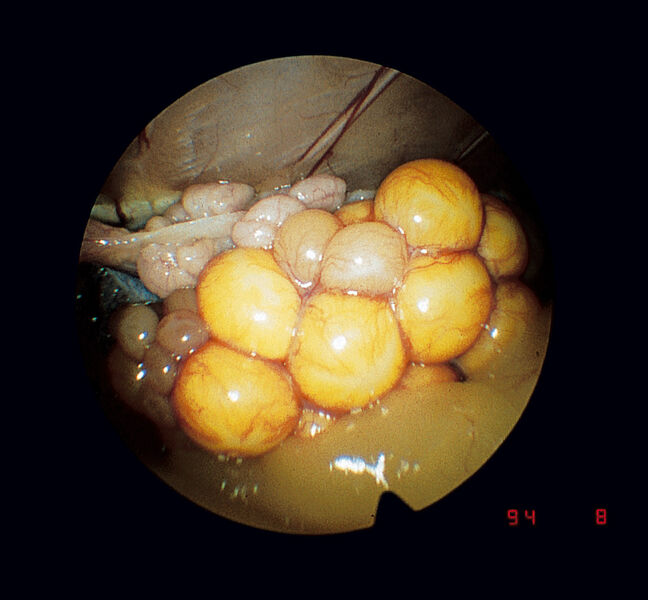

鳥類、両生類、小型ほ乳類、魚類に使用できる汎用内視鏡

- セリオスコピー、総排出腔鏡検査、膀胱鏡検査、鼻鏡検査、耳鏡検査、膣鏡検査、視覚管理下での挿管、口腔検査、性別判定、その他、多くの内視鏡手術や処置を行うことができます。